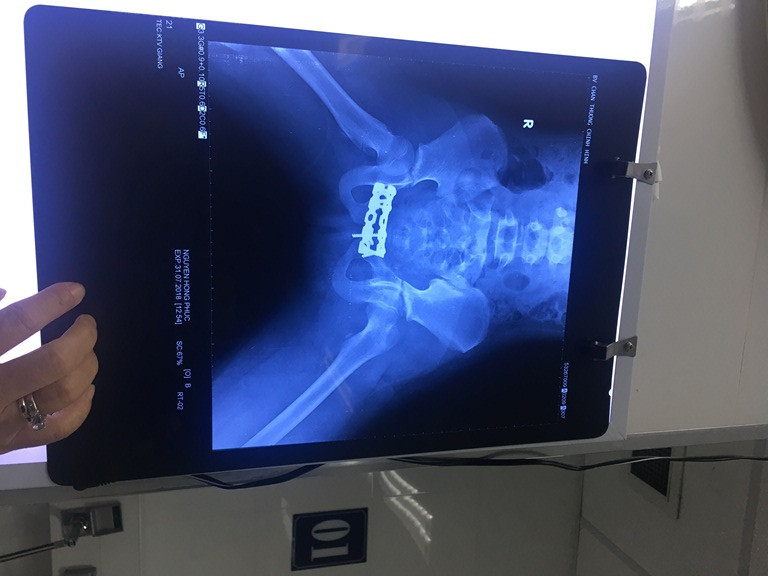

Xót xa bé 10 tuổi bị đứt lìa chân do tai nạn với xe tải ảnh 2Kết quả chụp CT chân bệnh nhân

Sáng ngày 31/7/2018, em đã được đưa vào phòng mổ để phẫu thuật cố định khung xương chậu. Hiện tình trạng của em đã ổn định và phục hồi tốt.